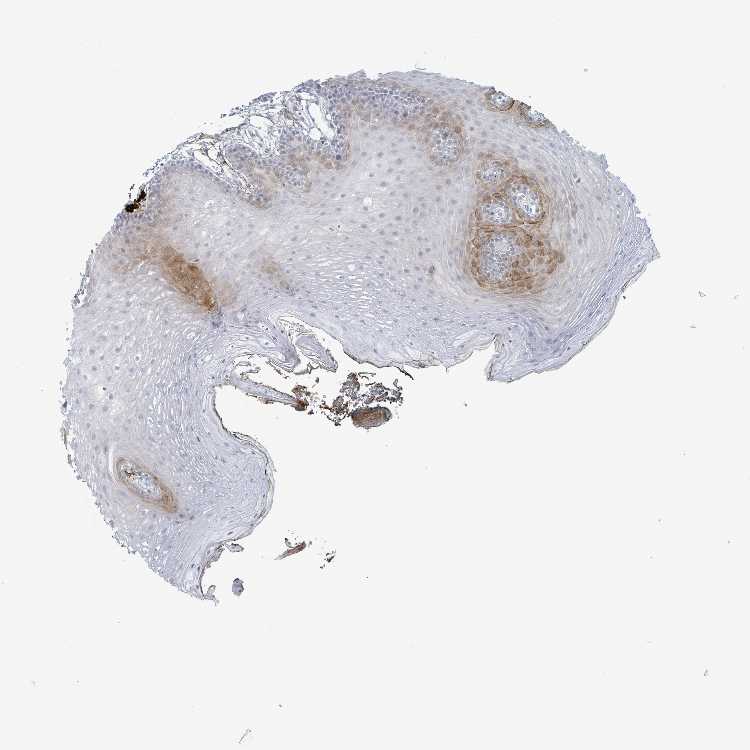

TISSUE PRIMARY DATA ORAL MUCOSA Show tissue menu

ORAL MUCOSA - Antibody stainingi

Antibody staining in the annotated cell types in the current human tissue is reported as not detected, low, medium, or high, based on conventional immunohistochemistry profiling in selected tissues. This score is based on the combination of the staining intensity and fraction of stained cells.

Each image is clickable and will lead to virtual microscopy that enables deeper exploration of all samples and also displays staining intensity scores, fraction scores and subcellular localization as well as patient and tissue information for each sample.

Antibody HPA050920

Squamous epithelial cells Medium